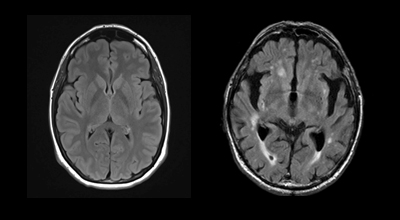

Les deux changements dégénératifs les mieux définis par les travaux sur la maladie d’Alzheimer sont les plaques séniles et les enchevêtrements neurofibrillaires. Ces lésions sont causées par des dépôts anormaux de protéines dans le cerveau, soit la bêta-amyloïde et la protéine tau. L’accumulation de ces deux lésions caractéristiques entraîne progressivement une perte dans le volume du cerveau. L’atrophie cérébrale visible à l’IRM (Figure 1) est particulièrement marquée dans les hippocampes, structures jouant un rôle majeur dans la mémoire. On remarque également un élargissement des ventricules, c’est-à-dire des cavités contenant le liquide céphalo-rachidien dans lequel baigne le cerveau à des fins de protection. Les enchevêtrements neurofibrillaires seraient les principaux responsables de ces détériorations.

Par la suite, des lésions variées des vaisseaux sanguins s’ajoutent au tableau. Elles sont causées par la maladie d’Alzheimer, mais également par divers facteurs de risque tels que l’obésité, le tabagisme, l’hypertension artérielle et le diabète. Ces lésions peuvent être visualisées à l’IRM sous forme d’hyperintensités de la matière blanche. En d’autres mots, la radiologie permet de détecter des zones « trop blanches » aux endroits affectés par des anomalies vasculaires, des infarctus et des saignements. Les lacunes sont de petits trous noirs qui peuvent aussi être aperçues sur les images des patients qui présentent des infarctus des artères plus profondes du cerveau.